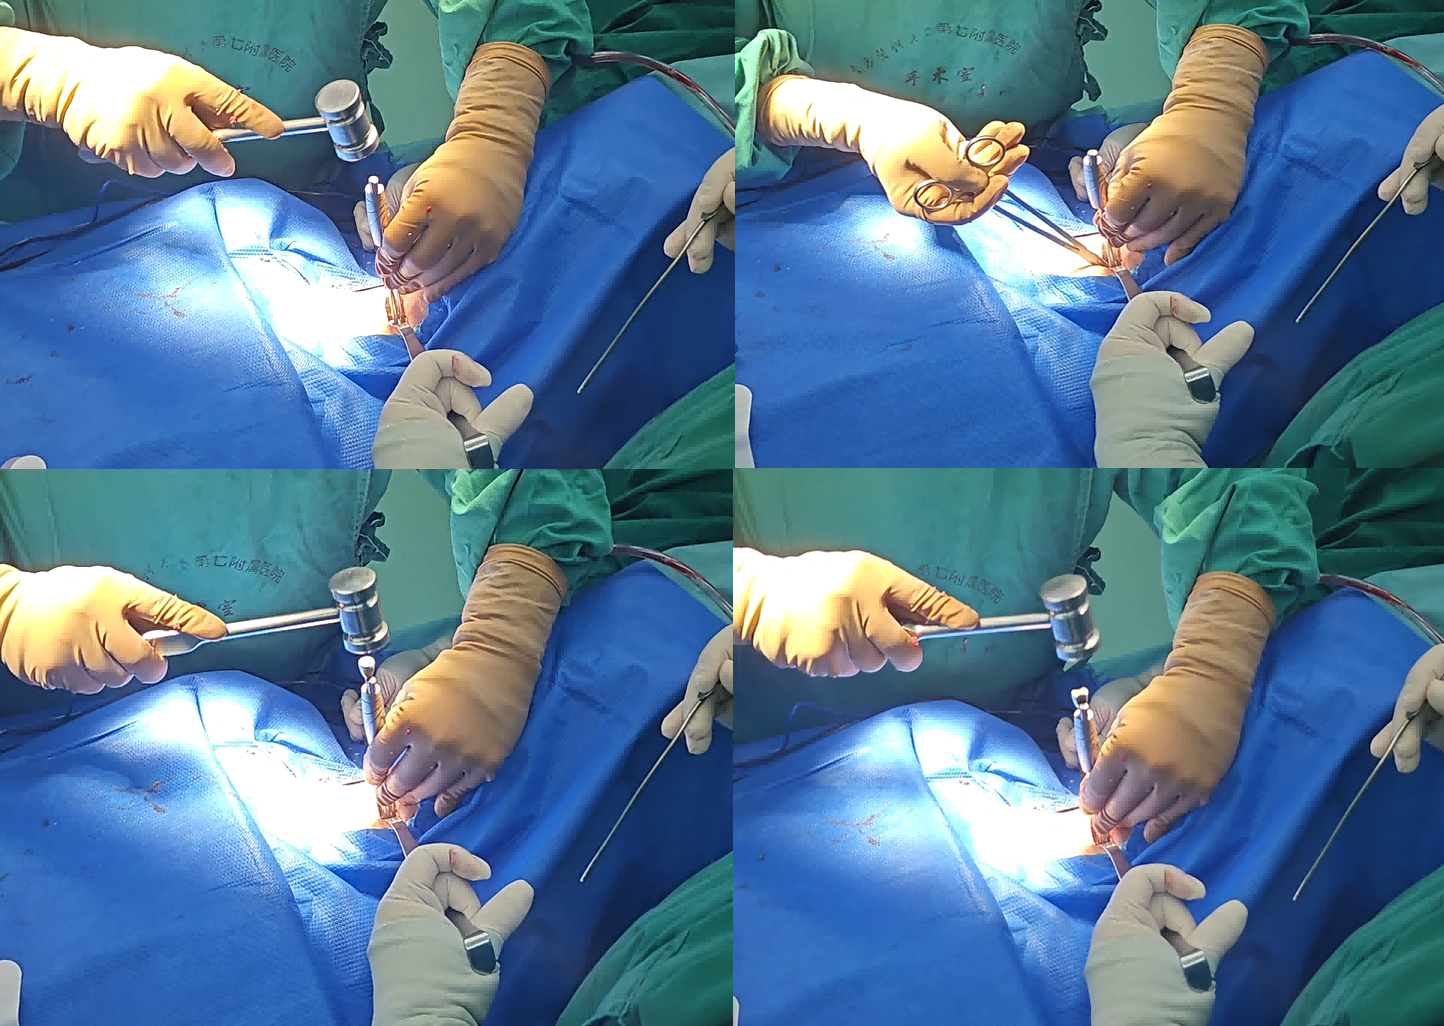

融合器及固定夹植入展示:

垂直于骨面敲入固定夹,高低位颈椎不被骨结构遮挡操作

器械占位小,更加微创;敲入即锁紧,更加便捷